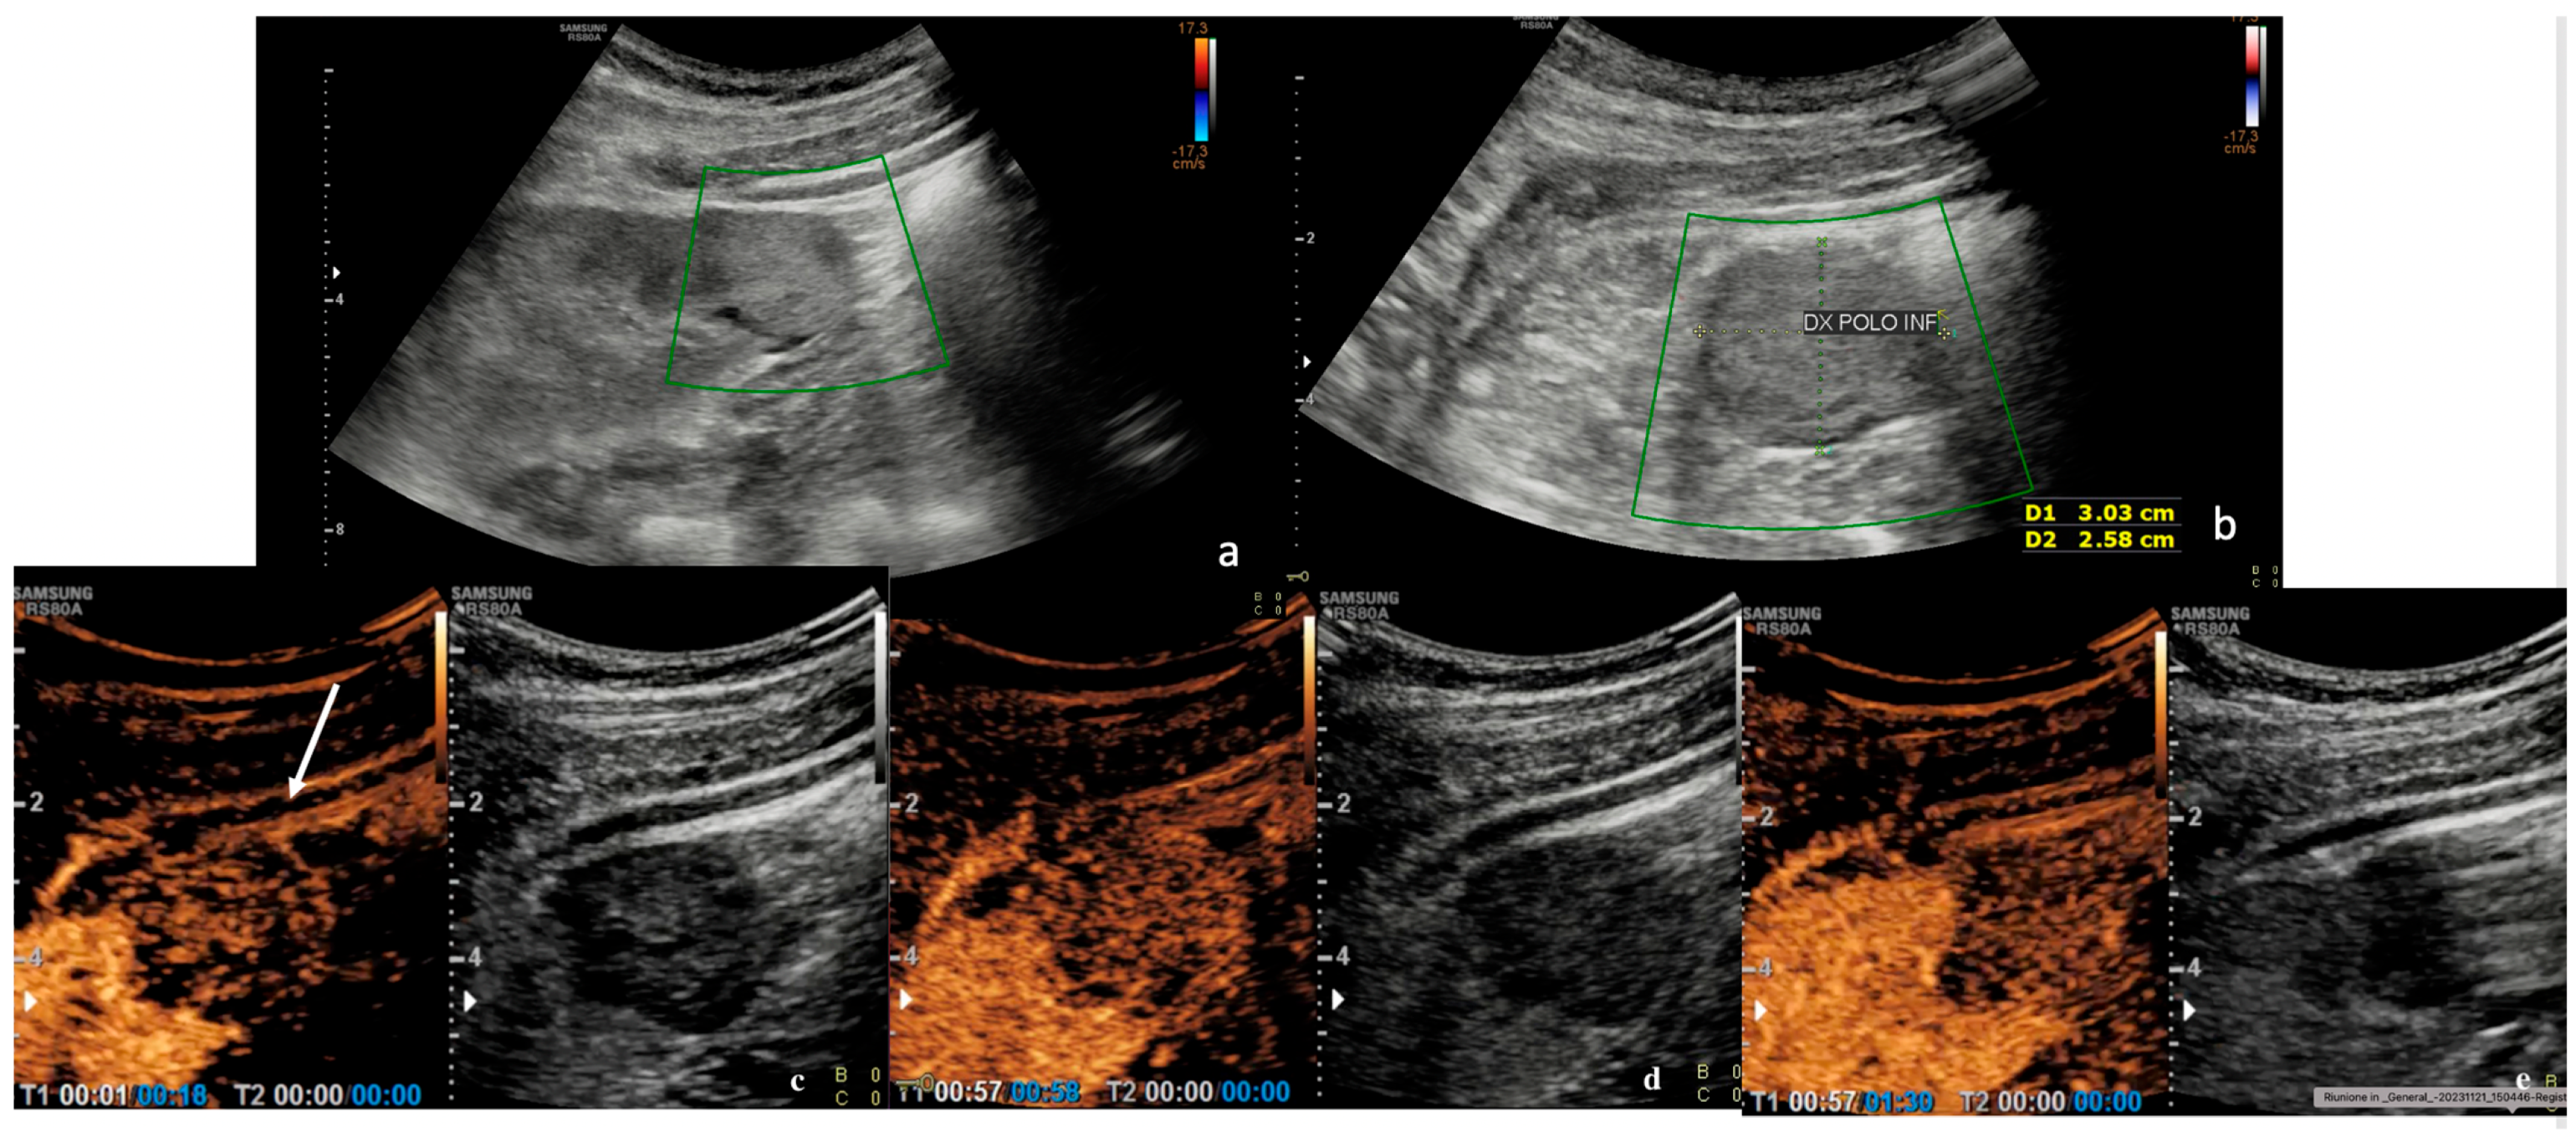

3.2. Contrast-Enhanced Ultrasound (CEUS)

| CEUS Features | % | n. | p > 0.05 |

| 70.3% | 19 | p < 0.05 |

| 29.7% | 8 | p > 0.05 |

| 0% | 0 | p > 0.05 |

| 52.2% | 12 | p < 0.05 |

| 29.6% | 8 | p > 0.05 |

| 25.9% | 7 | p > 0.05 |

| 62.9% | 17 | p > 0.05 |

| 37.0% | 10 | p > 0.05 |

| 81.5% | 22 | p < 0.05 |

| 11.1% | 3 | p > 0.05 |

| 7.4% | 2 | p > 0.05 |